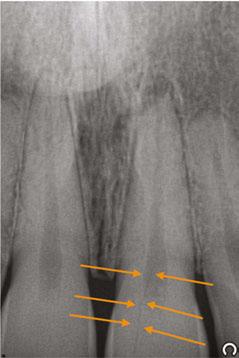

An 80-year-old male with a relatively clean medical history was referred for full-arch immediately loaded maxillary implant treatment. The patient had been previously treated with maxillary dental implants in a traditional All-on-X approach. The referring clinician noted that the patient’s bone was extremely “soft” and that insertion torque for most of the implants was very low. Although these implants were not immediately loaded, they ultimately failed and created large oroantral communications. While the communications were ultimately closed, extremely large

Figure 5 (left): CBCT slice (axial view) to determine Simmen classification.

Figure 6 (right): CBCT slice (axial view) for mediolateral measurement of prelacrimal bone width

Figure 7 (left): CBCT slice (sagittal view) for vertical measurement from subnasal bone to prelacrimal bone engagement point. Figure 8 (middle): Panoramic radiograph of patient with history of failed All-on-X treatment, oroantral fistulae, and thickened Schneiderian membranes. Figure 9 (right): Intrasurgical photo of transnasal dental implant traversing the nasal cavity and engaging the base of the inferior concha

defects resulted in the floor and walls of the maxillary sinuses (Figure 8). CBCT analysis revealed a significantly thickened left Schneiderian membrane and occluded osteomeatal complex. The patient was referred to ENT for a Functional Endoscopic Sinus Surgery (FESS) procedure. Upon healing, a new CBCT was taken and evaluated for potential treatment.